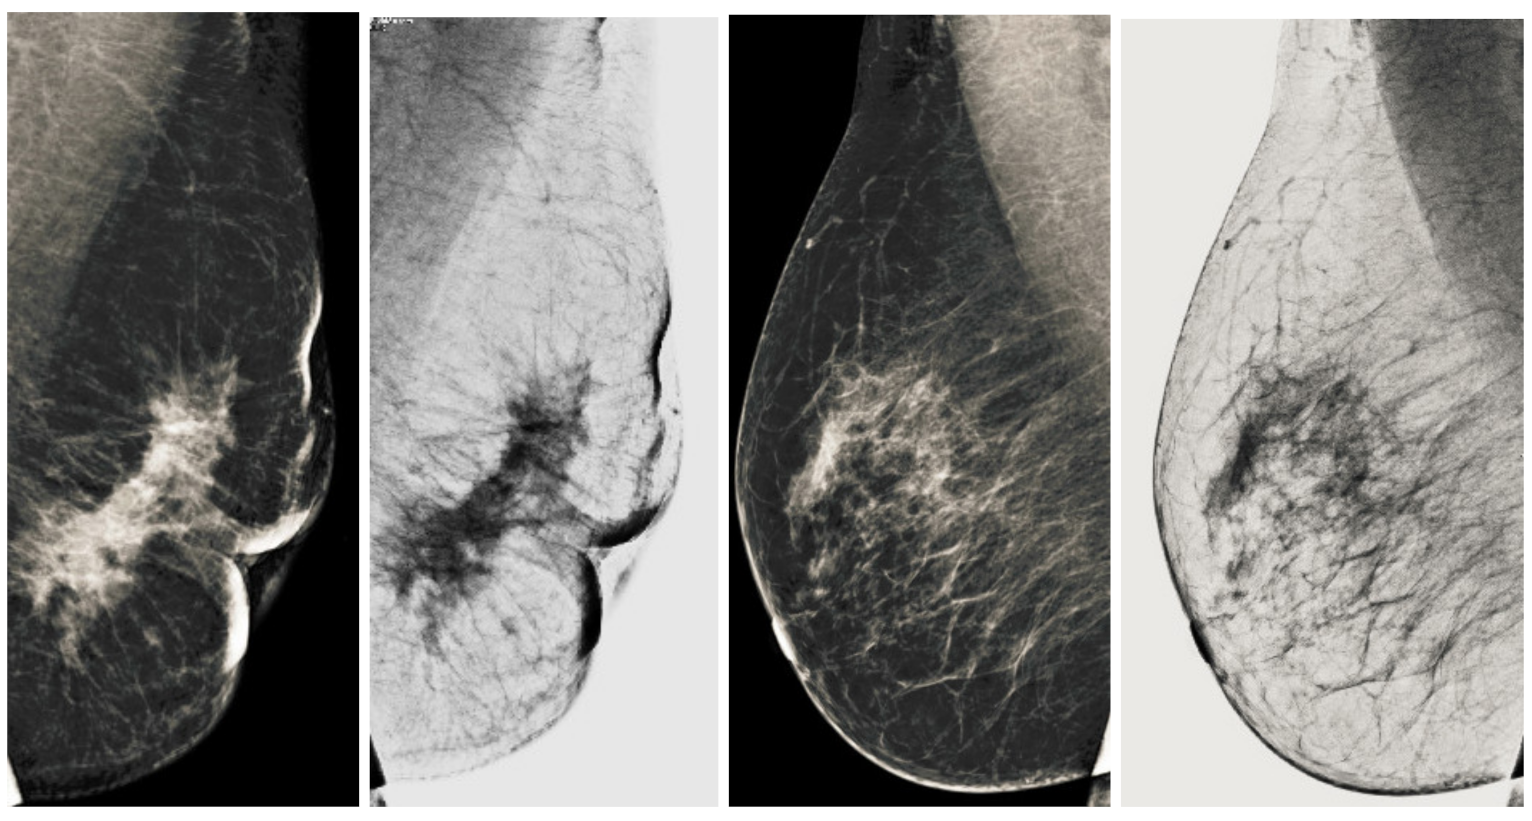

Figure 13.

Analysis of CC view of BI-RADS-4 mammogram images.

Figure 14.

Analysis of MLO view of BI-RADS-4 mammogram images.

Figure 15.

Analysis of CC view of BI-RADS-5 mammogram images.

Figure 16.

Analysis of MLO view of BI-RADS-5 mammogram images.

We also measured the PSNR, the image contrast, and the EME of each category of databases, as we analyzed the image in terms of visual observation. The Table 3 shows the performance of our proposed image enhancement method. It can be seen from the Table 3 that our proposed method improved PSNR, contrast, and EME, and this also shows that our method can work on every category of BI-RADS. Because many techniques do not work on higher grade BI-RADS due to the complexity and the images are not of good quality. We obtained an average improvement in PSNR, contrast, and EME in the Table 4. For more observations, we analyzed the visual image of each category and we analyzed the CC and MLO of each category as shown in the Figure 7, Figure 8, Figure 9, Figure 10, Figure 11, Figure 12, Figure 13, Figure 14, Figure 15 and Figure 16. From the figures, every detail of image of every category can be observed, leading to better segmentation of the abnormal region. This image enhancement technique can be used as preprocessing steps for the detection of breast cancer. It is a very fast processing algorithm and it takes on 21.13 s. It gives opportunity to medical experts to analyze the mammogram images very quickly to propose the timely treatment.